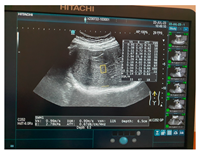

| Ultrasound | ![]() | ![]() | ![]() |